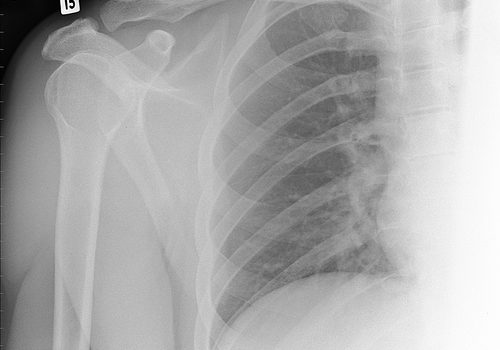

Identificado hormônio que tem impacto direto sobre a osteoporose

Ana María Silva, pesquisadora do Centro para Neurociência e Biologia Celular (CNC), da Universidade de Coimbra, ganhou o prêmio “Jovem Pesquisador” pelo seu trabalho em que avalia o metabolismo das células dos ossos na osteoporose depois da menopausa. Ler mais